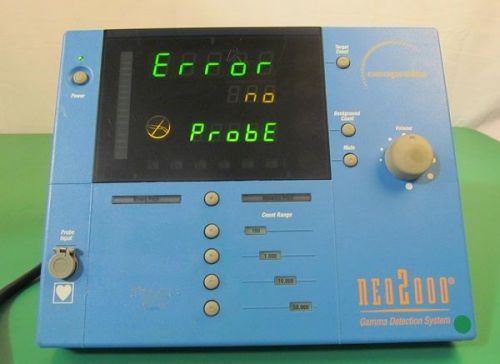

Neoprobe Neo2000 Gamma Detection System Counter